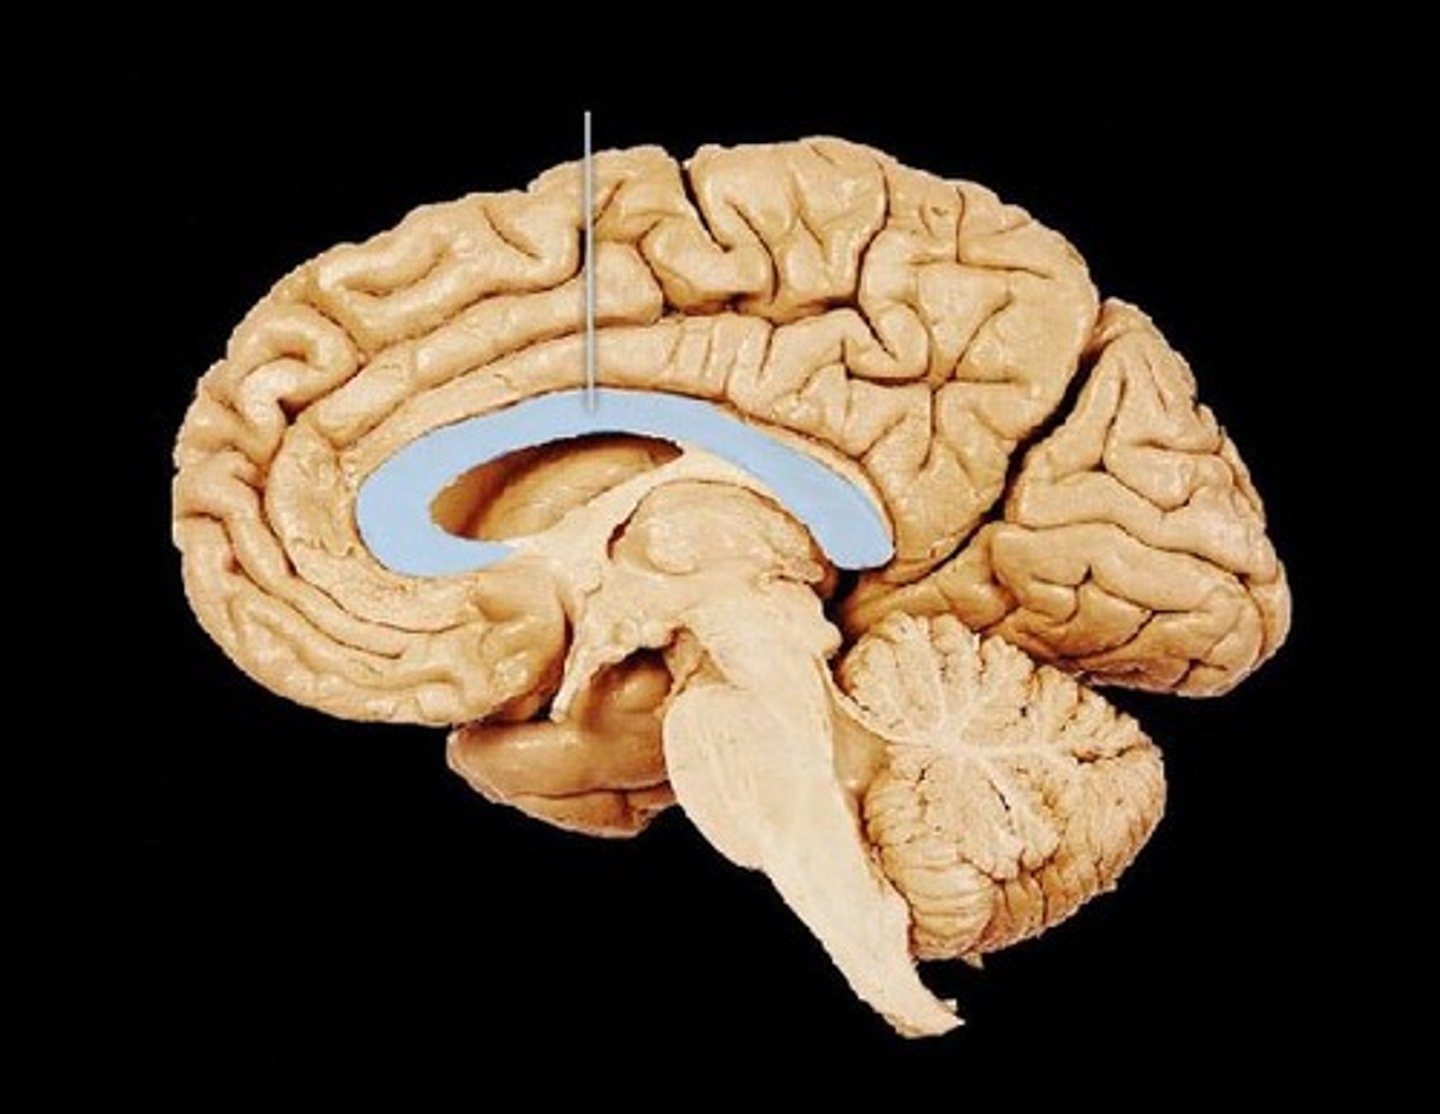

what are 3 key white matter structures found in the cerebrum?

1. corpus callosum

2. corona radiata

3. internal capsule

what cerebral white matter structure is a large bundle of nerve fibers that connects the left and right cerebral hemispheres, allowing them to communicate?

corpus callosum

what is the fan-shaped cerebral white matter sheet that is continuous ventrally with the internal capsule?

corona radiata

what cerebral white matter structure is a tract that carries sensory and motor information to and from the cerebral cortex?

internal capsule

what cerebral white matter structure is found between the basal ganglia?

internal capsule